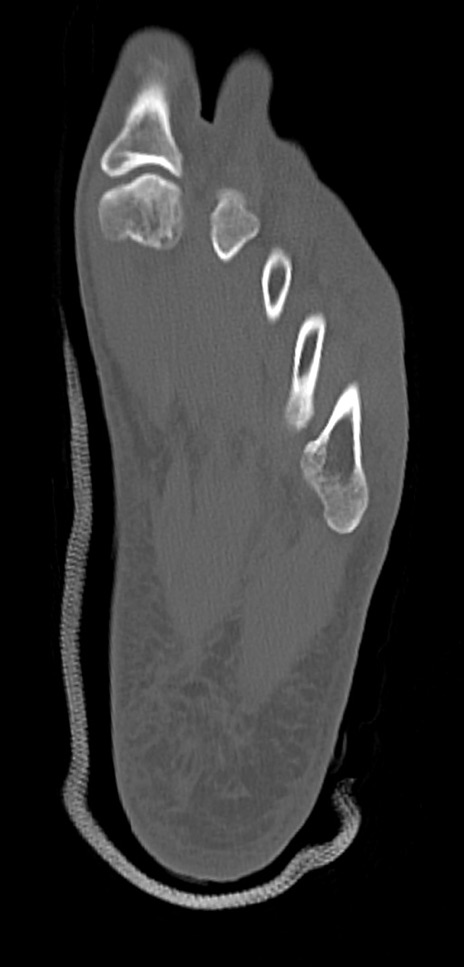

3D再構成